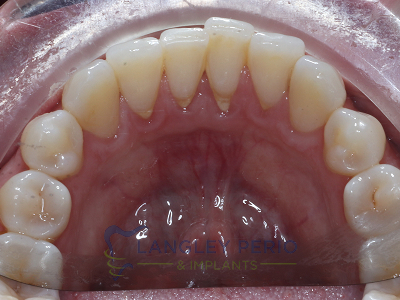

Case 3

Alloderm tissue grafting performed to improve root coverage and esthetics. This technique does not require tissue to be taken from the patient’s palate.